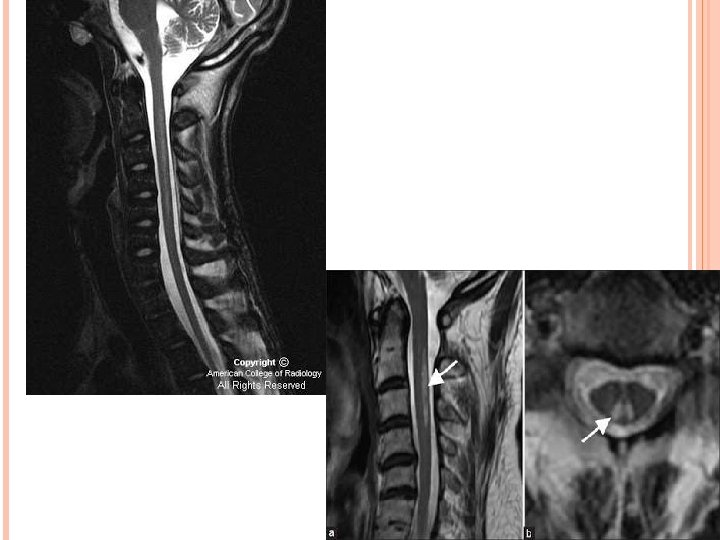

VACUOLAR MYELOPATHY OF SPINAL CORD. M/c chronic myelopathy associated with HIV, seen in late stage. C/C-Slowly progressive weakness of lower limb, gait disorders, sensory abnormalities in lower limb, impotency and urgency. MR-Spinal cord atrophy m/c affect the thoracic cord; cervical cord may be involved. -Bilateral symmetrical dorsal column involvement can be seen. D/D-SACD of cord.